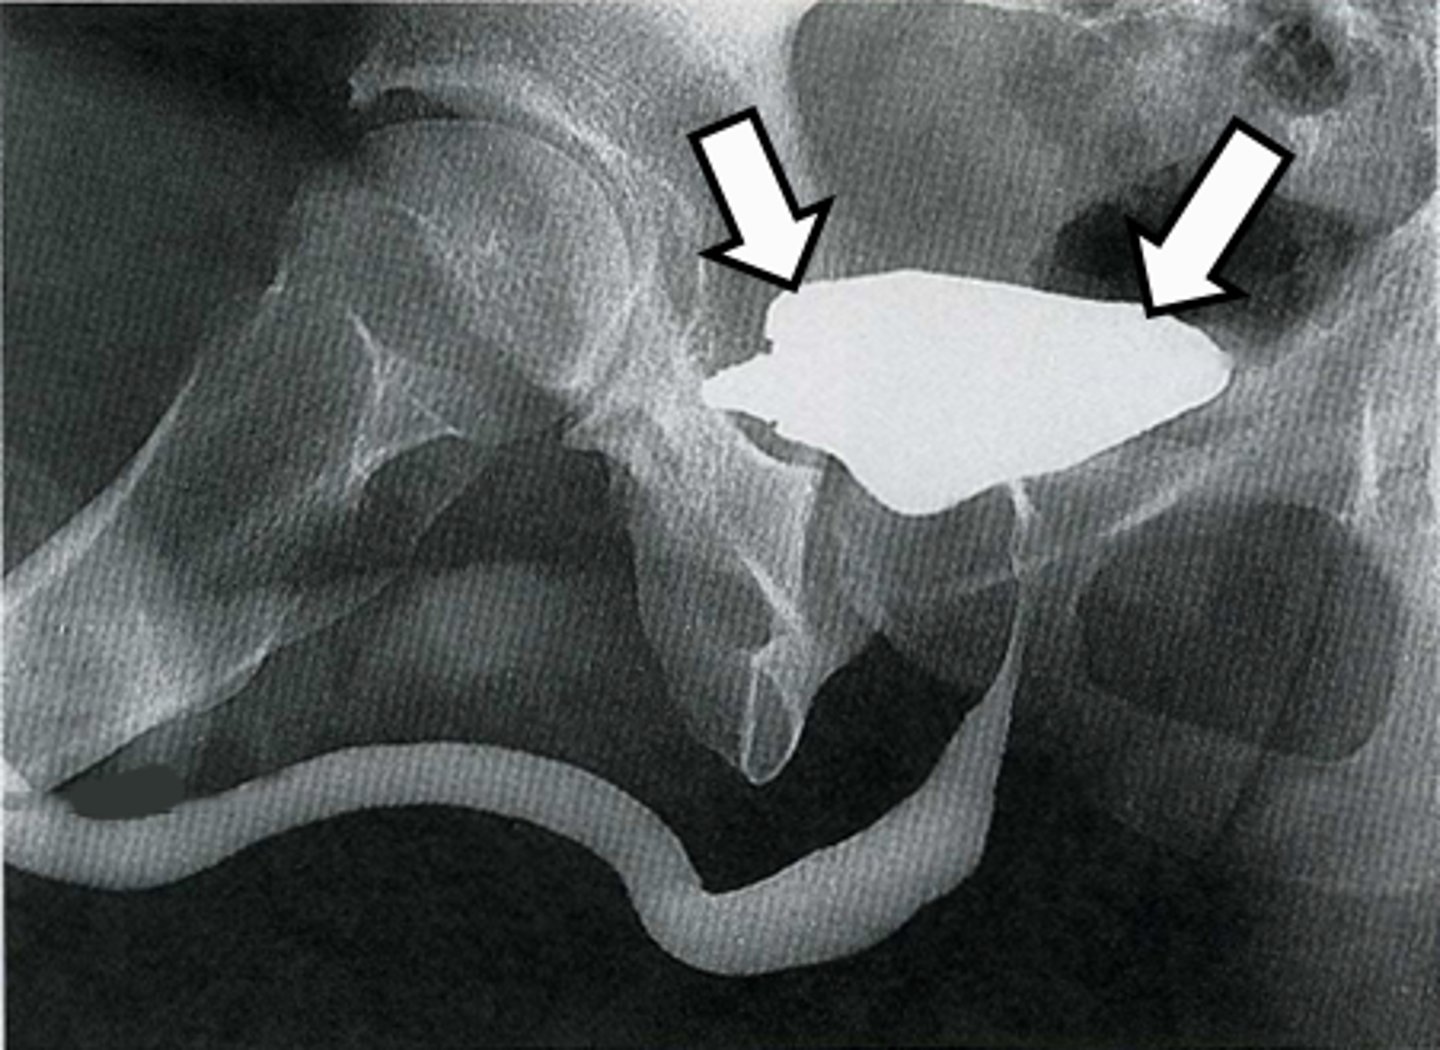

45

New cards

Intravenous pyelogram (IVP)

What is the image?

<p>What is the image?</p>